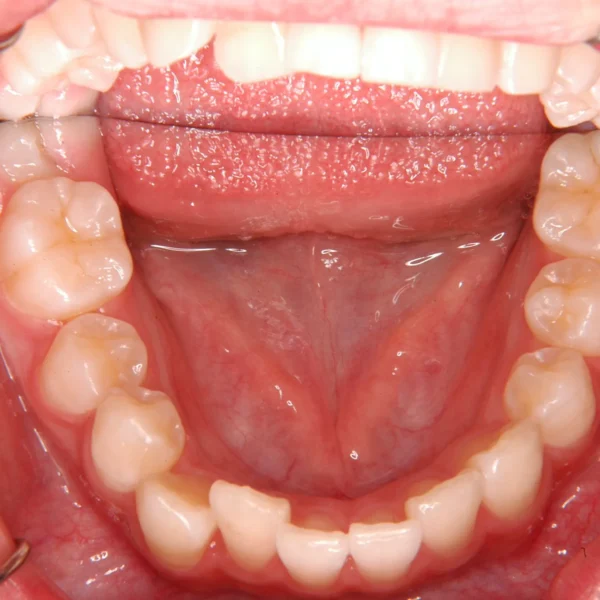

治療経過1